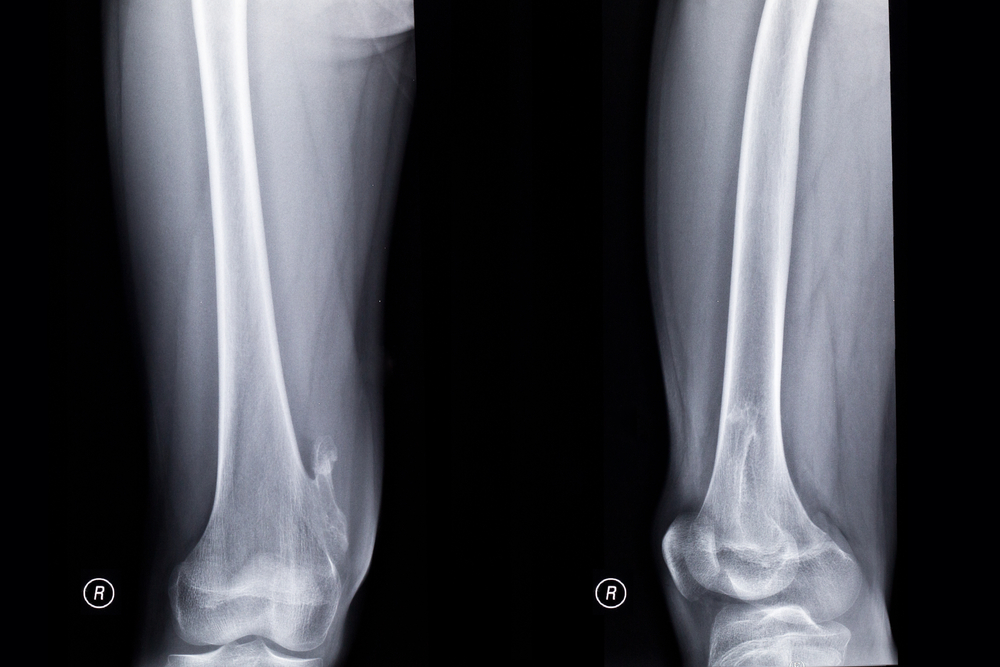

Рентгеновские снимки при центральных опухолях визуализируют присутствие в области кости очага с нечеткими контурами и неправильной формой (чаще образование располагается в метадиафизе). Костная ткань вокруг такой зоны вздута. Иногда опухоль может быть крапчатой – такой признак вызывается наличием очагов обызвествления.

При периферических опухолях на снимках визуализируется бугристое образование с нечеткими очертаниями. Оно контрастное и располагается на наружной части кости. На границе между новообразованием и здоровой костью отмечается уплотнение неравномерного характера. В этой области кортикальный слой костной ткани неровный. Иногда, как и при центральных опухолях, визуализируется крапчатость, вызванная очагами обызвествления.